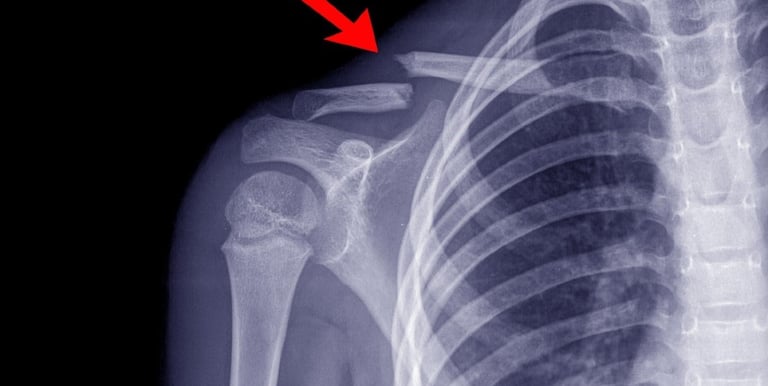

Tratamento de fraturas e deformidades ósseas

Fratura é a perda da continuidade óssea, isto é, quando acontece a quebra de um osso, mesmo que não seja completa. O tratamento pode ser conservador através da redução e imobilização com colocação de tala, gesso ou imobilizadores específicos. Mas também pode ser realizado tratamento cirúrgico, com a fixação por meio de hastes, placas e fios metálicos, além de fixadores externos e artroplastias.